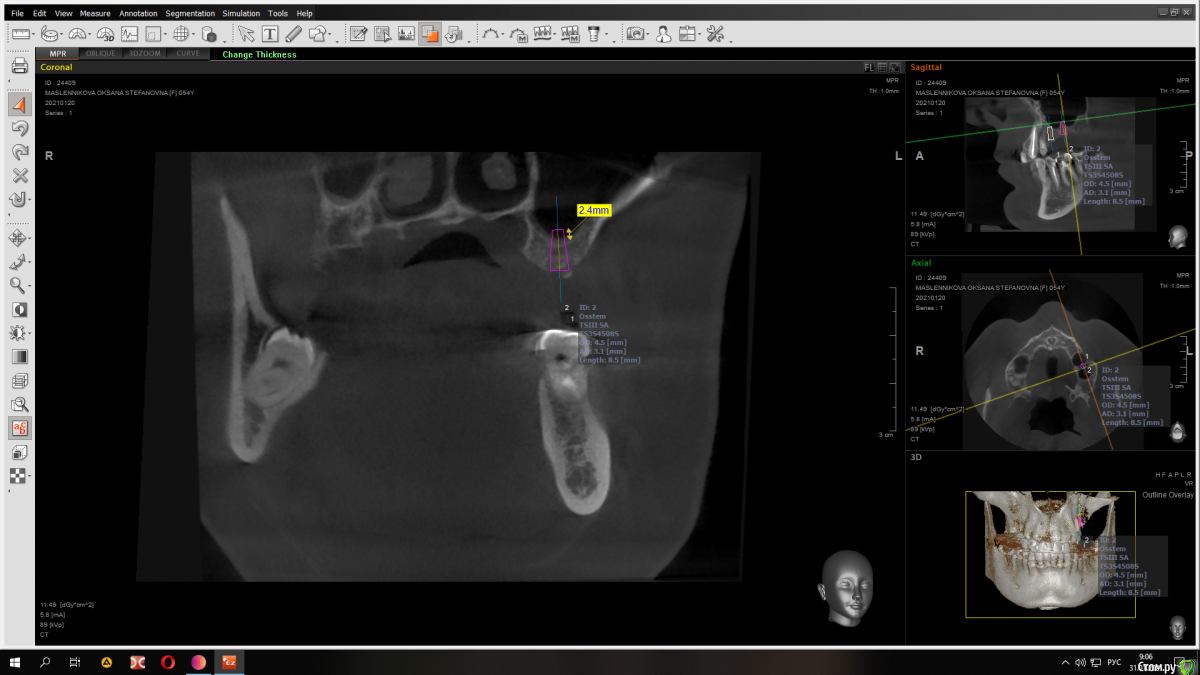

Raystom Опубликовано 31 января, 2021 Автор Поделиться Опубликовано 31 января, 2021 Конечно) Вот вариант с 8.5 мм имплантатом Ссылка на комментарий

red_butler Опубликовано 31 января, 2021 Поделиться Опубликовано 31 января, 2021 Имхо замеры сделаны не правильно, но не вижу проблем. Если нет остеотомов, то закрытый синуслифт можно выполнить имплантом 1 Ссылка на комментарий

Raystom Опубликовано 31 января, 2021 Автор Поделиться Опубликовано 31 января, 2021 Имхо замеры сделаны не правильно, но не вижу проблем. Если нет остеотомов, то закрытый синуслифт можно выполнить имплантом в чем ошибка в замерах? Ссылка на комментарий

red_butler Опубликовано 31 января, 2021 Поделиться Опубликовано 31 января, 2021 в чем ошибка в замерах?замеры используя шаблон импланта Ссылка на комментарий

Fin Опубликовано 2 февраля, 2021 Поделиться Опубликовано 2 февраля, 2021 Коллеги, в данном случае какую длину имплантата Вы посоветовали? Как Вы считаете нормально ли в данном случае брать импл. 8.5 и он будет в гайморовой на 2,5 мм? Или лучше взять покороче? Ссылка на комментарий

red_butler Опубликовано 3 февраля, 2021 Поделиться Опубликовано 3 февраля, 2021 Коллеги, в данном случае какую длину имплантата Вы посоветовали? Как Вы считаете нормально ли в данном случае брать импл. 8.5 и он будет в гайморовой на 2,5 мм? Или лучше взять покороче?8-9 мм Ссылка на комментарий